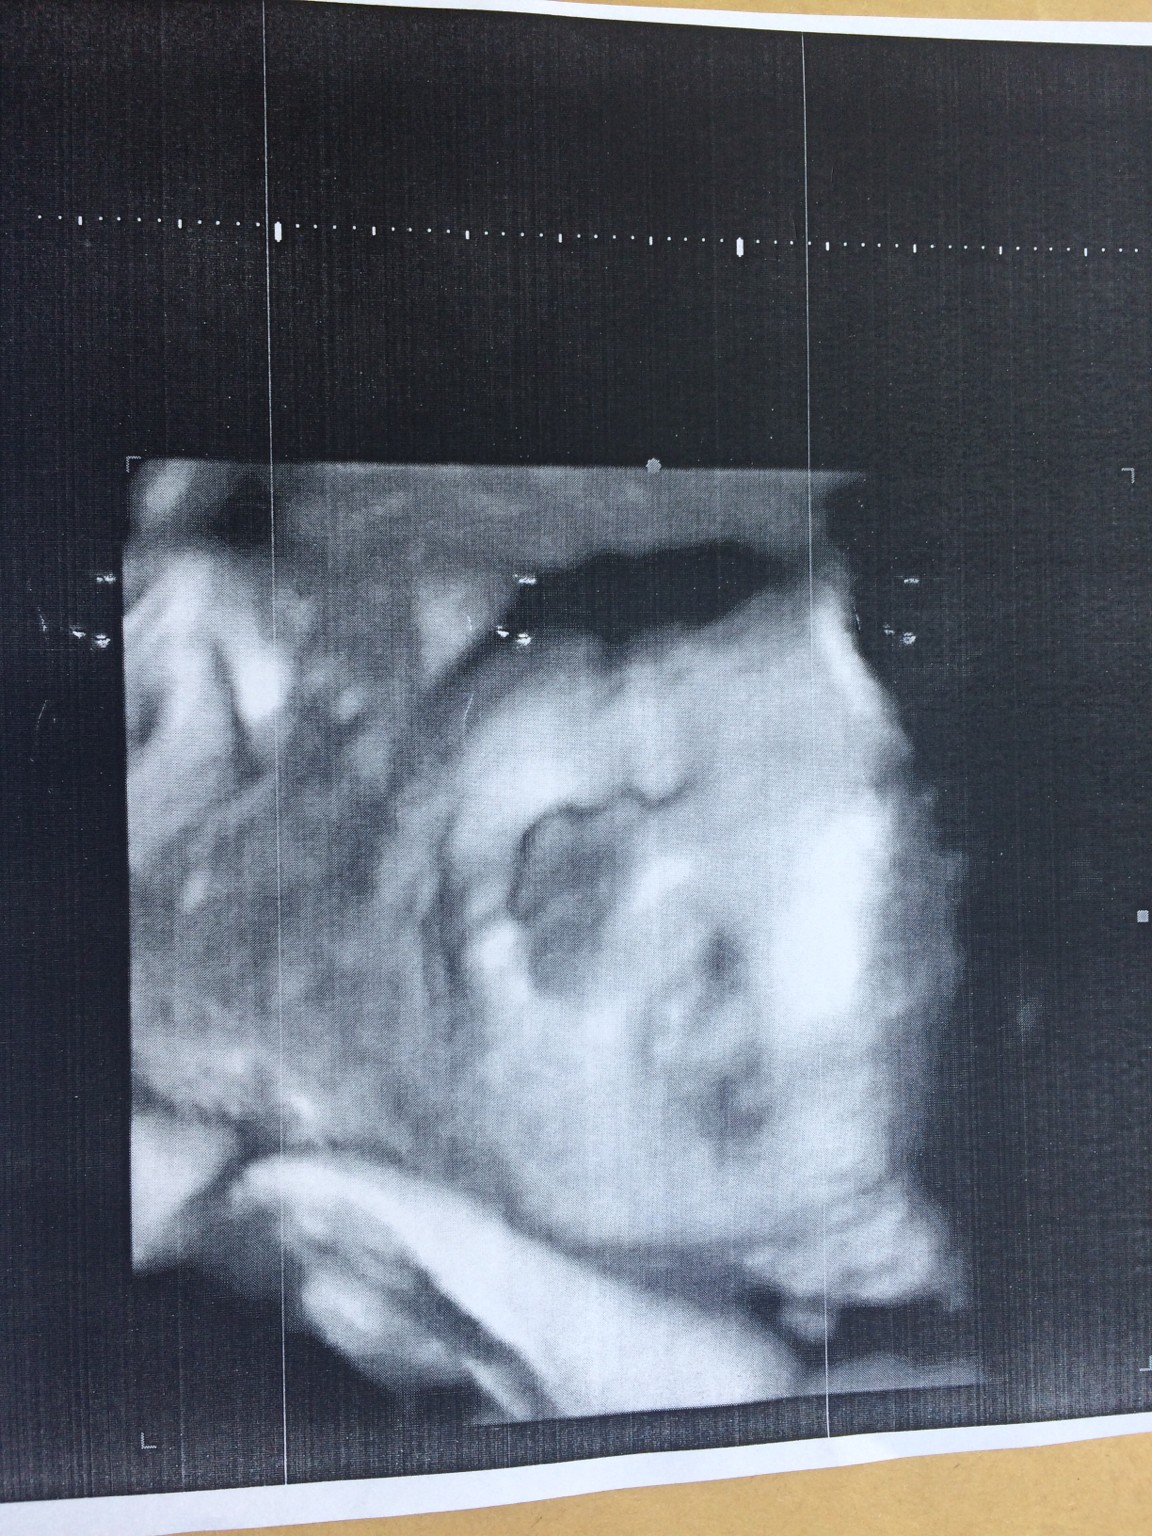

Mała jest blisko główka łożyska i tylko jedno zdjęcie udało się zrobić, ale i tak jestem zakochana po uszy.

Mój Bartek mówi, że cała ja.

Zobacz załącznik 866345